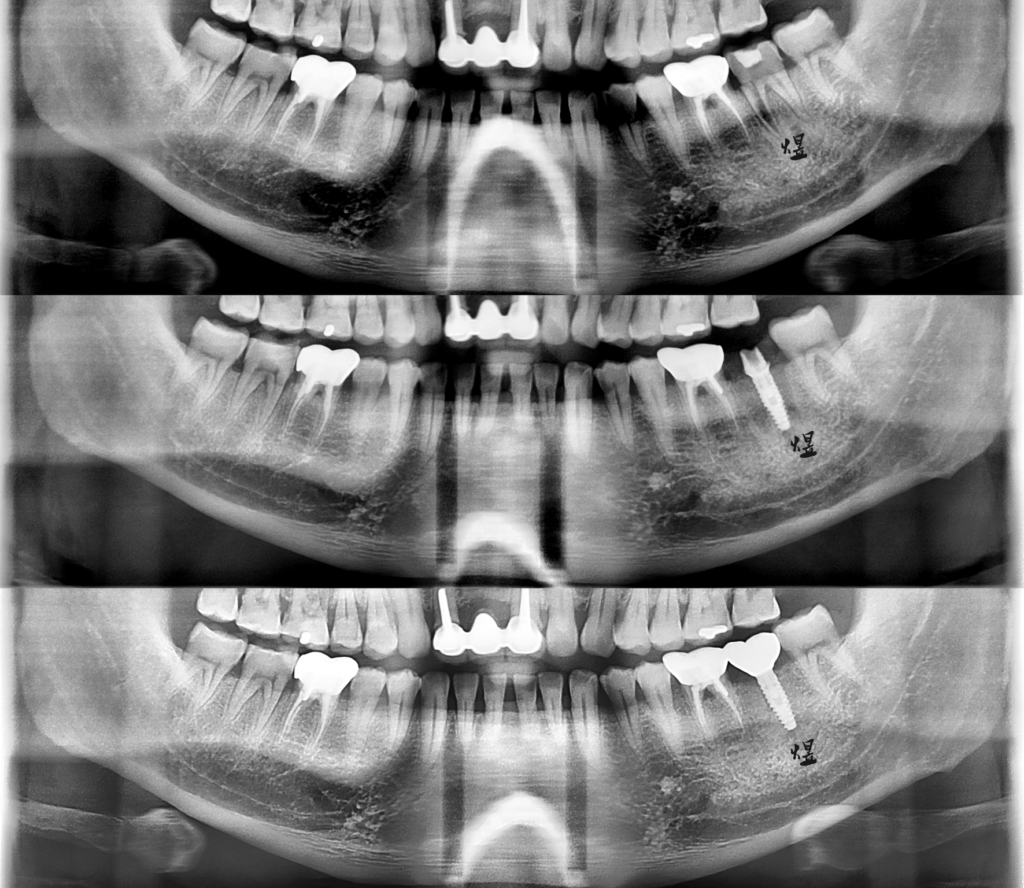

病患牙齒斷裂,同一天完成即拔牙以及人工植牙。

以未來假牙的位置,規劃手術導引板(水晶牙齒),路徑精準安全。

水晶牙齒保留與維持最大量拔牙前軟硬組織的結構與型態;縮短手術時間,微創舒適、更減少製作臨時假牙的時間,不用在診間過度久候。